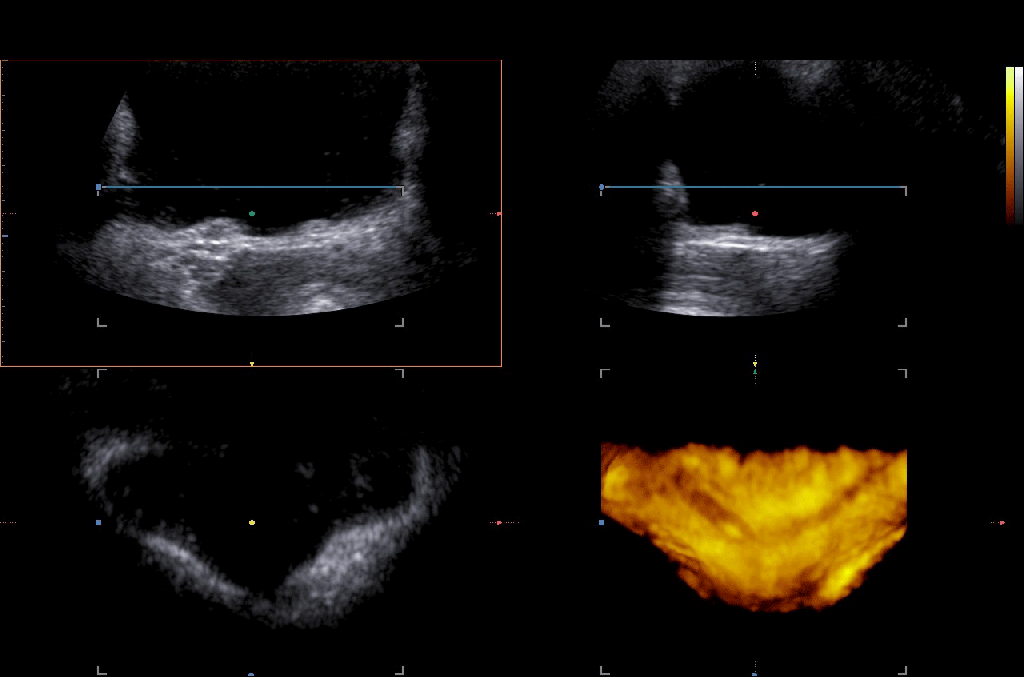

The abdominal ultrasound examination began with an intact pregnancy and a mild maternal hydronephrosis on the right side. The transvaginal sonography showed a distal ureteral calculus with dilatation of the right distal ureter.

The ureteric stone is perfectly visible with transvaginal sonography.

The stone only measured 3.4mm and after conservative treatment (analgetics and hydration) the patient managed to pass it.